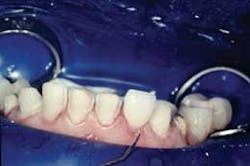

The excess cement is removed with a Bard Parker 12B scalpel blade. Minimal polishing is done with Sof-Lex™ Extra Thin Superfine Discs (3M ESPE) and Flexibuffs™ with Porcelize polishing paste (Cosmedent). The remaining veneers are seated in pairs following the same protocol (Fig. 9).